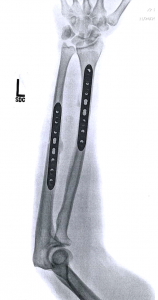

Unfortunately the new hardware did not come with superpowers: no unbreakable bones or retractable claws, only increased TSA scrutiny.